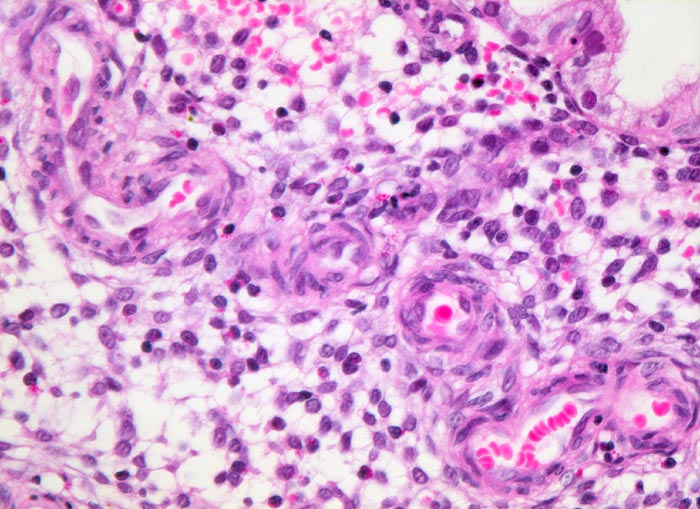

Endometrioide Karzinome bestehen aus tubulären Drüsen, welche von einem mehrreihigen Epithel ausgekleidet werden. Schleim ist meist nicht oder nur apikal in den Zellen vorhanden. Die Ausdehnung der soliden Areale und die zytologischen Atypien bestimmen den Differenzierungsgrad (low-grade versus high-grade). Metaplastisches Plattenepithel findet sich häufig in endometrioiden Karzinomen und hilft bei der Abgrenzung von anderen Subtypen. Das endometrioide Karzinom kann sich innerhalb von Adenomyoseherden im Myometrium entwickeln (> 4482). In diesen Fällen kann die Bestimmung der Infiltrationstiefe erschwert sein.

• Tumorzellverbände infiltrieren die glatte Muskulatur des Myometriums.

• Tumordrüsen ausgekleidet von mehrreihig angeordneten Tumorzellen mit hyperchromatischen polymorphen längsovalen Tumorzellkernen mit zahlreichen Mitosen. Die Morphologie der Tumordrüsen erinnert an proliferatives Endometrium.